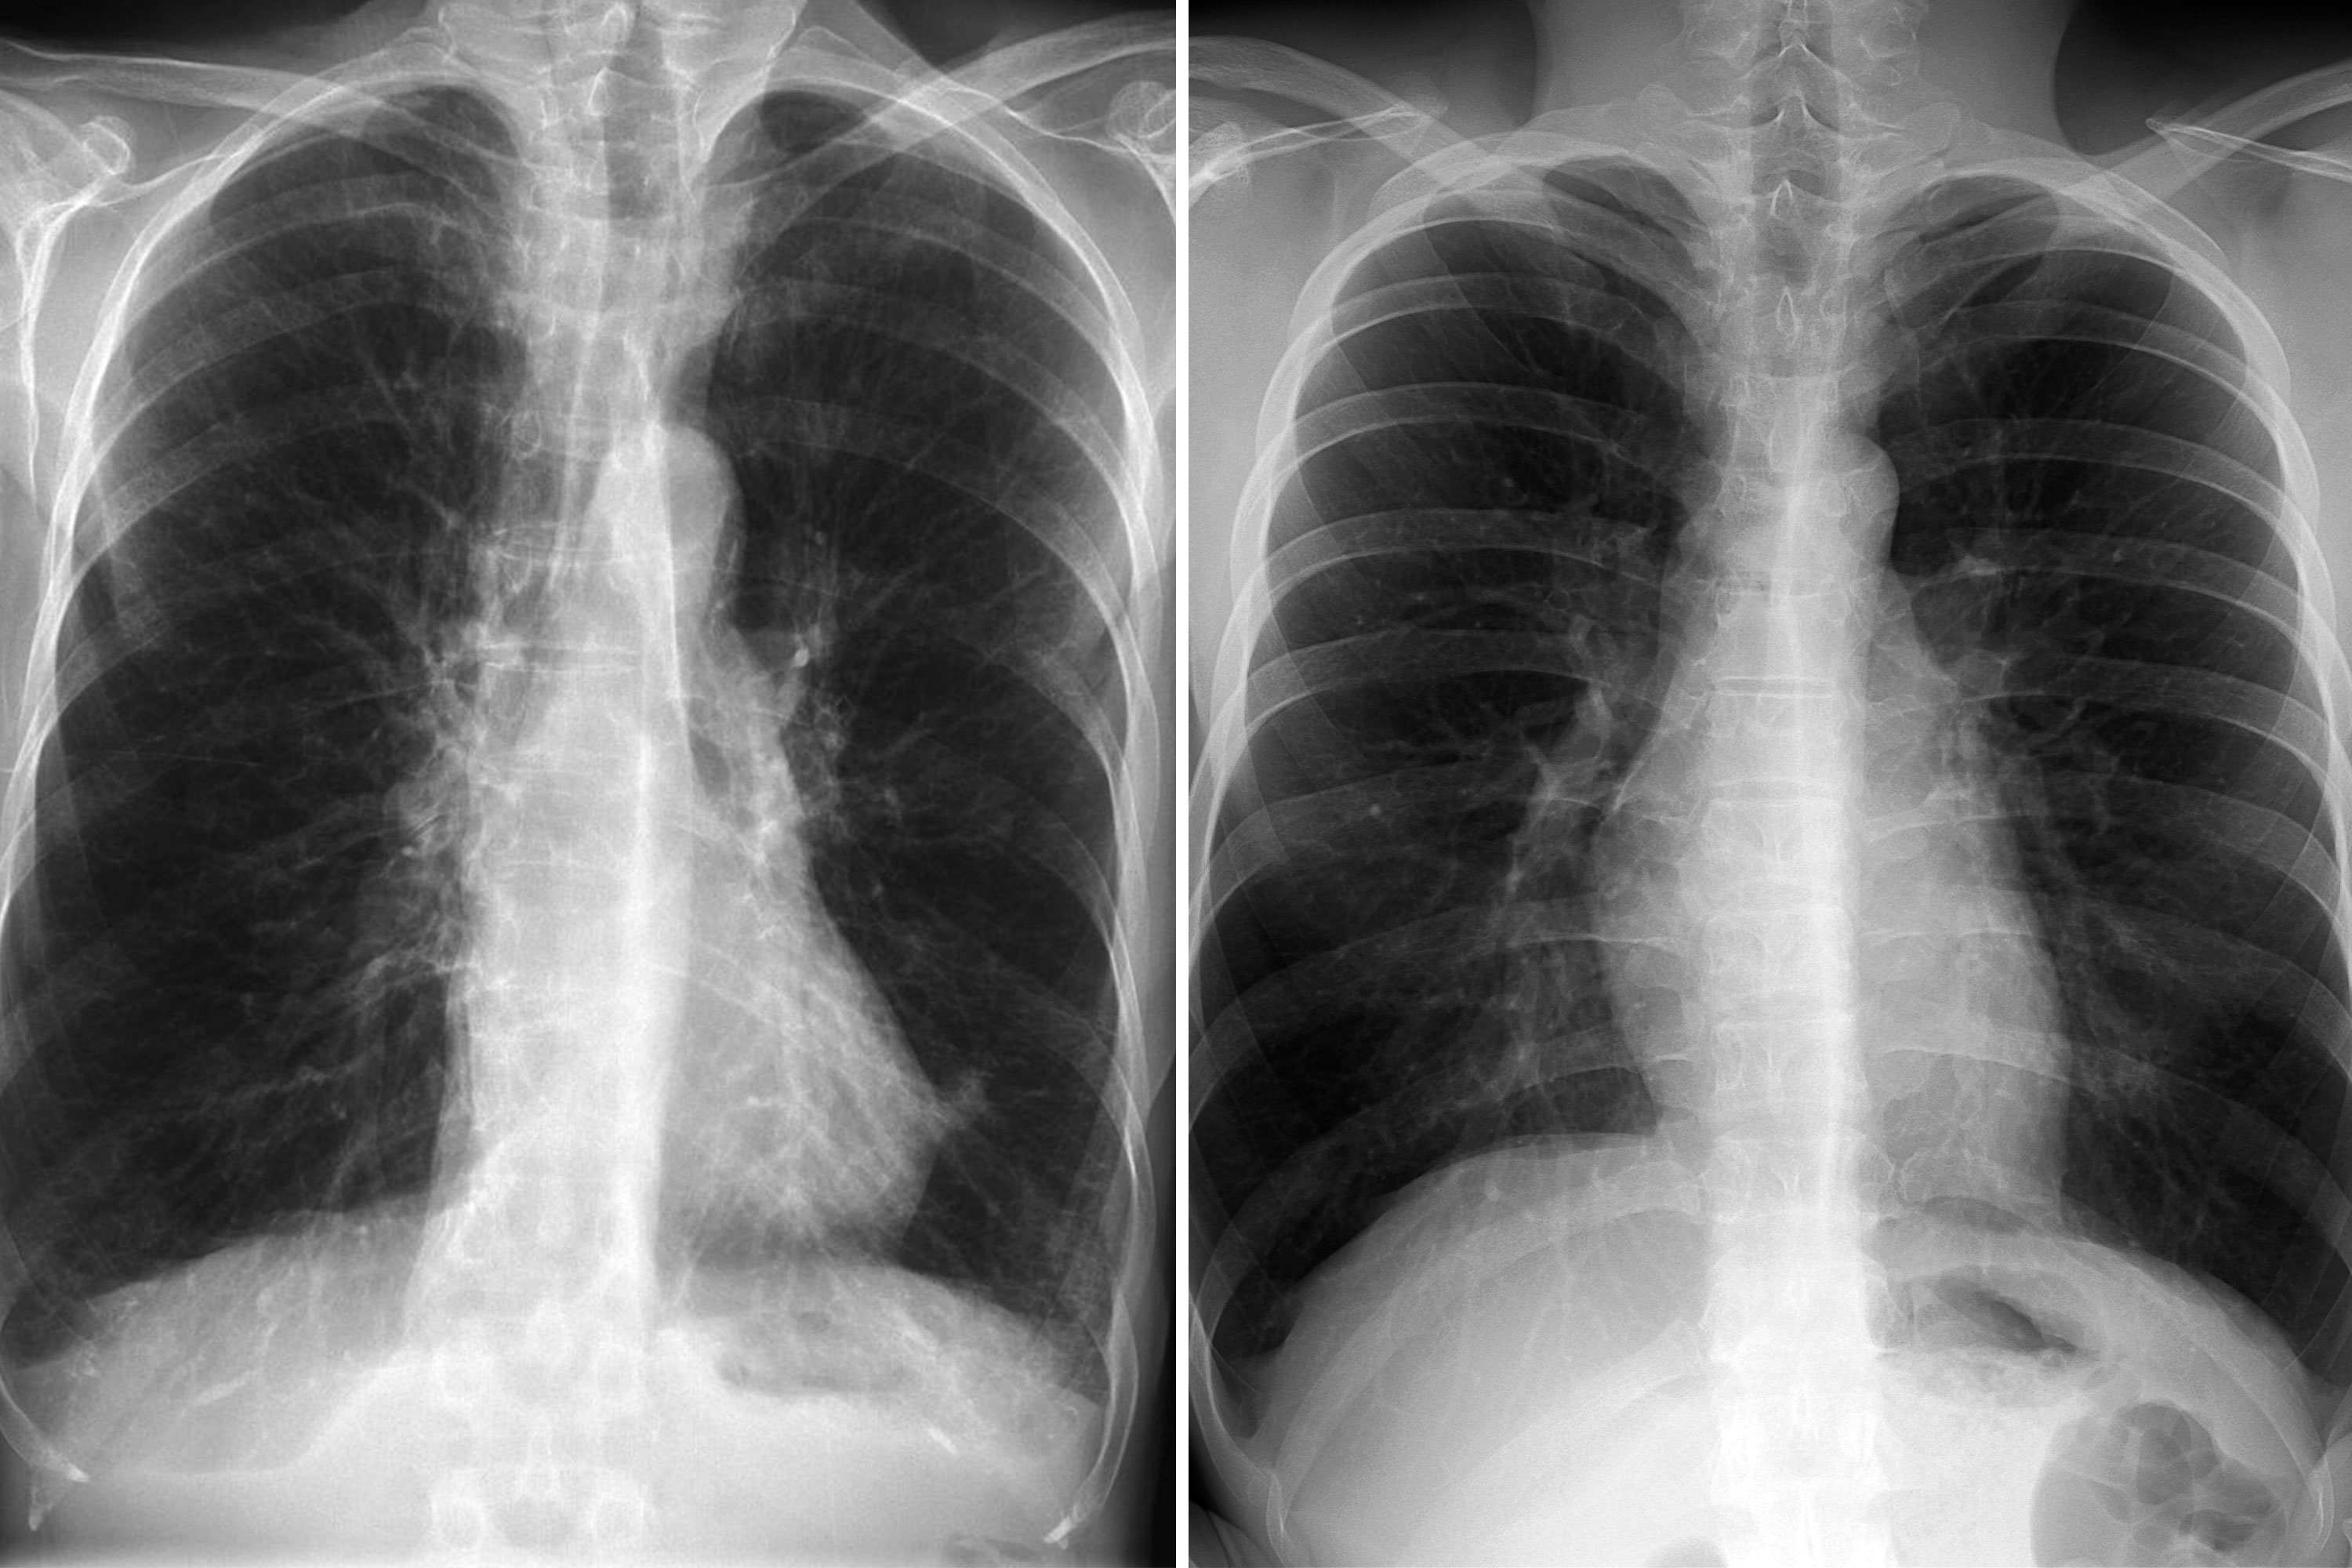

Understand the anatomy and clinical significance of the lingula of left lung. This guide details this unique bronchopulmonary segment, its anatomical position, common respiratory conditions, and diagnostic imaging techniques. Learn how this specific area relates to lung health and pathology, helping you navigate complex pulmonary anatomy with clarity and expert-backed insights for better medical understanding.